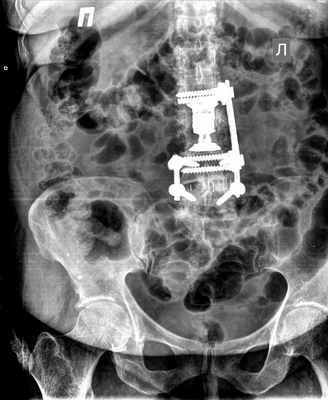

31.03.2016 операция: микрохирургическая декомпрессия корешков спинного мозга на уровне L3, L4-L5, межтеловой спондилодез на уровне L2-L4 имплантом Obelisk и пластиной Vantage, на уровне L4-L5 имплантом Oracle из левостороннего бокового доступа с использованием нейрофизиологического мониторинга.

Рис 5. Послеоперационный рентген-контроль: удаленное тело L 3 позвонка замещено межтеловым имплантатом Obelisc , проведена дополнительная стабилизация вентральной пластиной Vantage , исправлена кифотическая деформация поясничного отдела позвоночника.

04.04.2016 операция: Микрохирургическая декомпрессия корешков спинномозговых нервов на уровне L4-L5 справа. Транскутанная, транспедикулярная фиксация системой Expedium Viper II на уровне L4-L5 с двух сторон.

Рис 6. Послеоперационный рентген-контроль. В межтеловом промежутке L 4-5 находится кейдж Fidji , транспедикулярная система фиксации Expedium Viper 2 на уровне L 4-5.